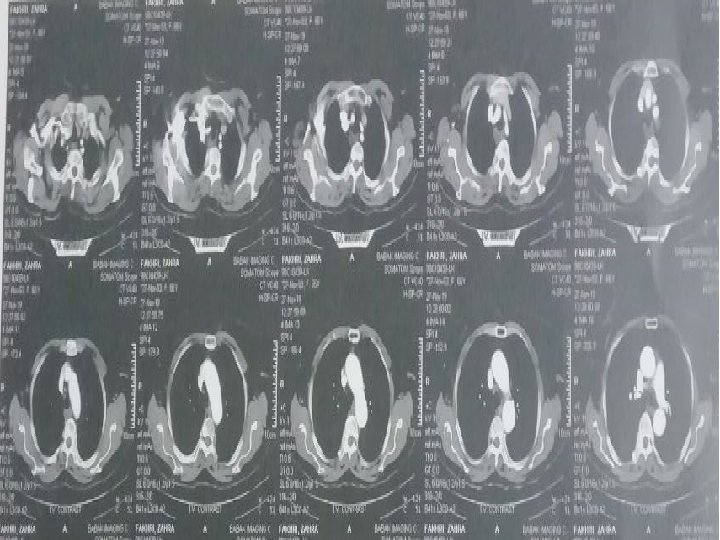

CT scan of chest with and without contrast 98/6/9